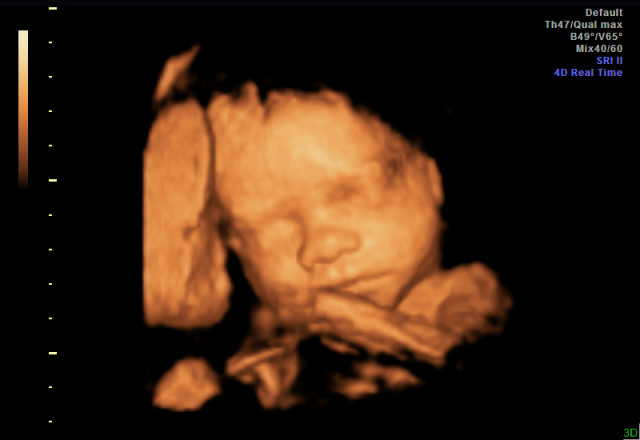

Yesterday I had a 3d ultrasound and it was an amazing experience! Before having it done, I wasn't sure if it was worth the money, but after, I can say that it is for sure worth every penny! The ultrasounds I've had at the doctor's office have been very short, rushed, and not detailed at all. With the 3d ultrasound, we got to see every part of the baby and in great detail. She even yawned and hiccupped while we were watching, which was adorable! If anyone is considering it and on the fence, you should do it and you will be so happy you did.